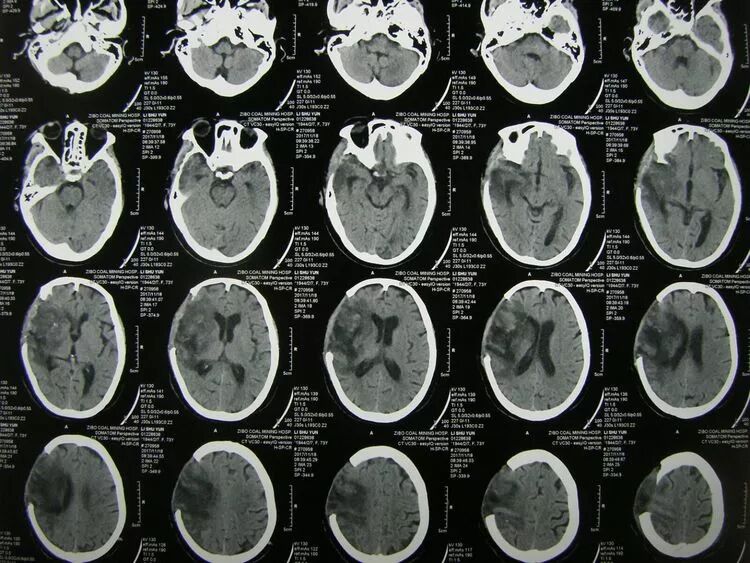

术后患者瞳孔恢复至等大,意识好转,刺激睁眼,cT复查:血肿清除满意,中线复位,三脑室及脑池显示清楚。

术后2周CT复查,水肿基本消退,中线良好,脑池清晰,脑室无扩张。